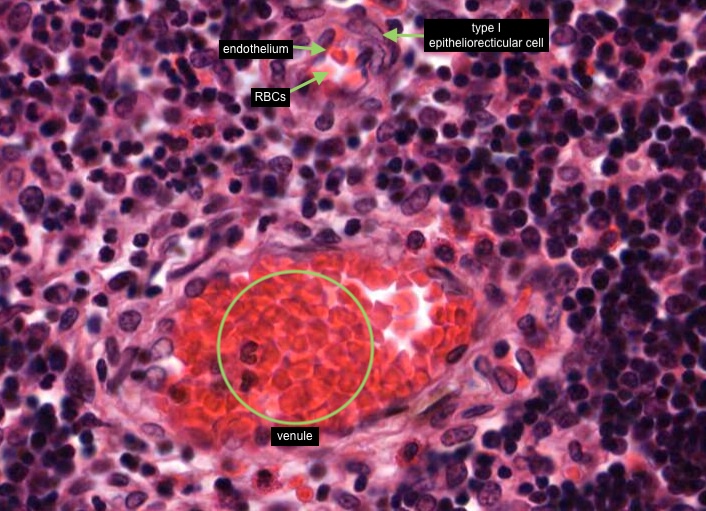

All lymphocytes that enter the cortex of the thymus are not able to contact antigen because of the blood-thymus barrier - it is a physical barrier. The structures that constitute the blood-thymus barrier are endothelium lining the capillary wall (identified by the presence of a few red blood cells) and maybe a pericyte that may be also present, any macrophage in the vicinity/perivascular connective tissue and a type I epithelioreticular cell.

You can see similar components of the blood-thymus barrier around the venule in this image.